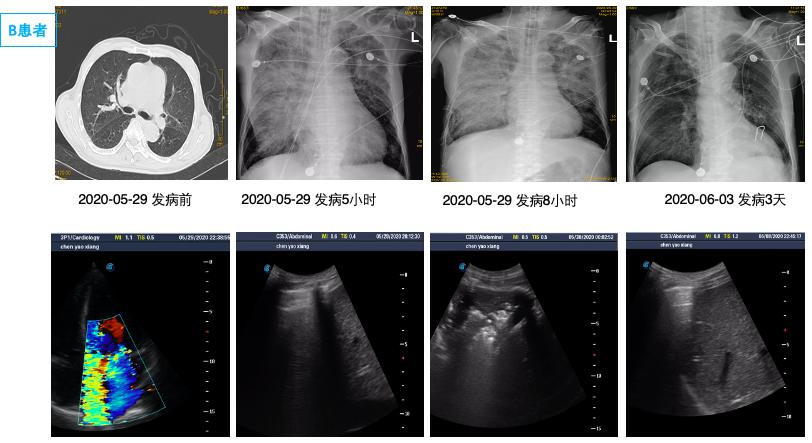

(A1、A2为同一患者,左侧PE,男,65岁,A1为发病前,A2为心脏骤停4 h后。B1、B2为同一患者,右侧PE,男,68岁,B1为心脏骤停后4 h后,B2为治疗3 d后。) 图 1 单侧肺水肿胸片表现 Fig 1 Manifestations of unilateral PE on X-ray

通过病历系统回顾性分析2018年1月至2021年1月,共纳入314例患者,其中男性179例,女性135例,年龄18~97岁[(58.8±16.9)岁]。单侧PE患者共14例,发病率4.5%,男性10例,女性4例; 其中以右侧为主单侧PE 11例(78.5%),左侧PE患者3例(21.5%)。1例单侧PE呈右肺上叶局限性分布,(见图患者C),1例单侧PE以左下肺为主(见图患者A),其余单侧PE分布无明显肺段特点。